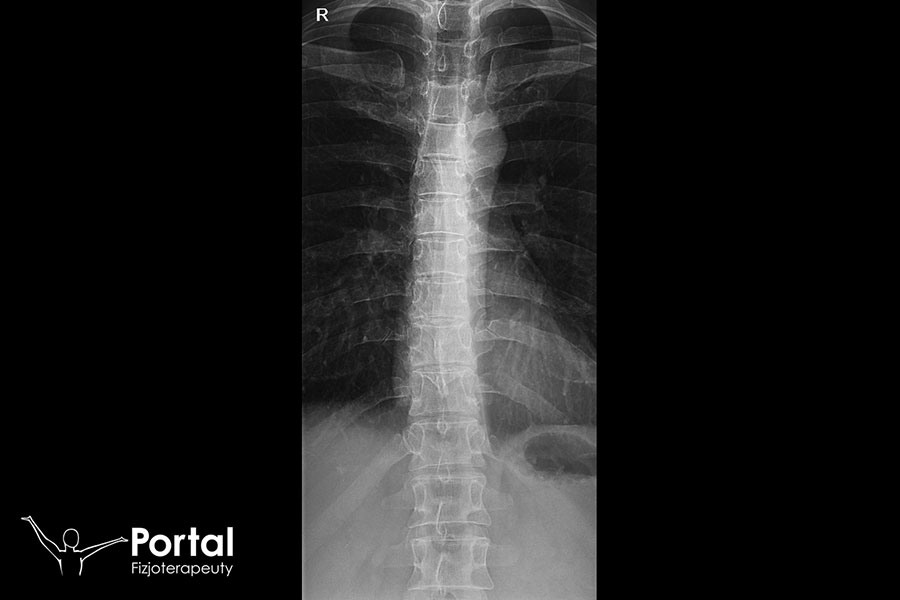

Odprostowanie lordozy szyjnej określane jest również jako jej zniesienie. To bardzo częsty problem XXI wieku, na co w dużej mierze